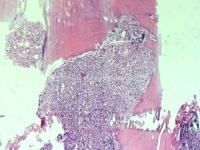

性别

男

年龄

74岁

腰骶部疼痛不适2月余 CT示骶髂处溶骨性改变伴周围软组织肿胀

骶髂处骨组织活检

1*1*0.5cm灰红碎组织

建议:CK;EMA;S-100等,排除脊髓瘤的可能性!(CT诊断什么?)

浆细胞性骨髓瘤或髓系肿瘤应考虑……